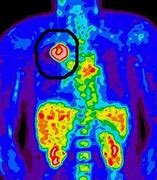

• PET-CT

PET-CT

Se invento la tomografía por emisión de positrones y la tomografía computarizada de una forma que hace que sea mas fácil para los médicos el localizar tumores y diferentes estructuras en las imágenes, con lo que es la combinación de ambas máquina se hace menos costoso para los médicos y para los hospitales tener el acceso para ambas formas tecnología.